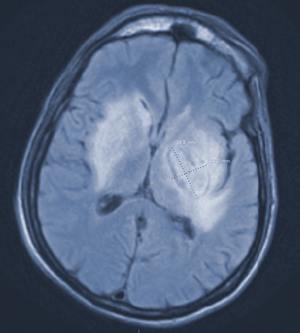

Clinicians review a patient case including diagnosis, treatment, and follow-up.